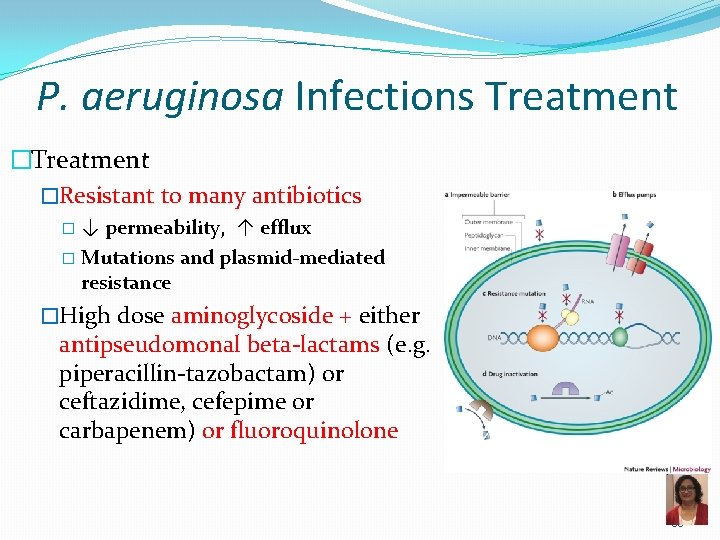

P. aeruginosa Infections Treatment �Resistant to many antibiotics �↓ permeability, ↑ efflux � Mutations and plasmid-mediated resistance �High dose aminoglycoside + either antipseudomonal beta-lactams (e. g. piperacillin-tazobactam) or ceftazidime, cefepime or carbapenem) or fluoroquinolone 35